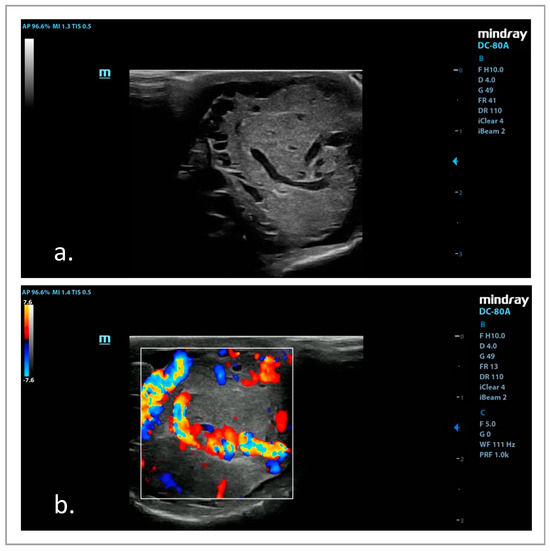

3.3. B-Mode and Doppler US Examinations

3.4. SWE Examinations